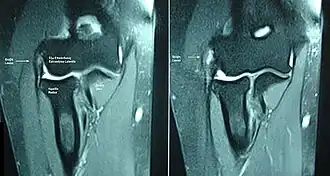

Epicondylitis lateralis, (backhand-)tenniselleboog of tennisarm is een pijnlijke chronische prikkelingstoestand in de arm. De term is enigszins misleidend omdat de aandoening vaker door andere overbelastende bewegingen dan tennis wordt veroorzaakt en het geen ontsteking (-itis), maar een abnormaliteit (-osis) is.

Het betreft de pezen die aanhechten aan de epicondylus lateralis van het opperarmbeen (humerus). Deze pezen zijn de uiteinden van de handstrekkers, de extensorspieren van de onderarm die onder meer zorgen voor het strekken van de pols, hand en vingers.

Beeldvorming is vaak niet nodig om de diagnose te maken.